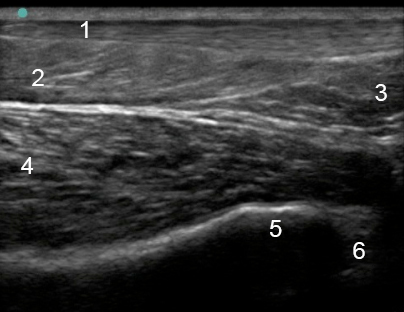

Image - Cheville postérieure : Cheville supérieure, Coupe sagittale moyenne

1. Tendon calcanéen

2. Muscle soléaire

3. Paquet adipeux de Kager

4. Tendon du long fléchisseur de l'hallux (LFH)

5. Tibia

6. Talus